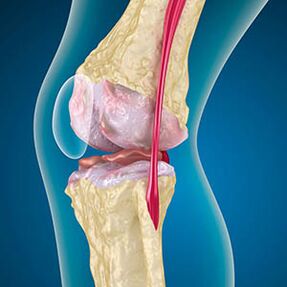

Met artrose is het kraakbeen langs de randen van de botten slijtage of volledig afwezig. Beschadigd weefsel is geen bron van pijn, omdat het geen receptoren heeft. Ontsteking bij structuren in de buurt veroorzaakt karakteristieke symptomen.

Het lichaam zet de regeneratie van beschadigde weefsels voort, maar het kraakbeen groeit ongelijk. Als gevolg hiervan worden onregelmatigheden gevormd die andere elementen van het gewricht verwonden. De aard van osteofyten wordt verklaard door compensatie voor glad gewricht kraakbeen. Een andere versie geeft aan dat de groei van "sporen" Het wordt geassocieerd met een poging om het gewricht mediaal of lateraal te stabiliseren als gevolg van spierverzwakking.